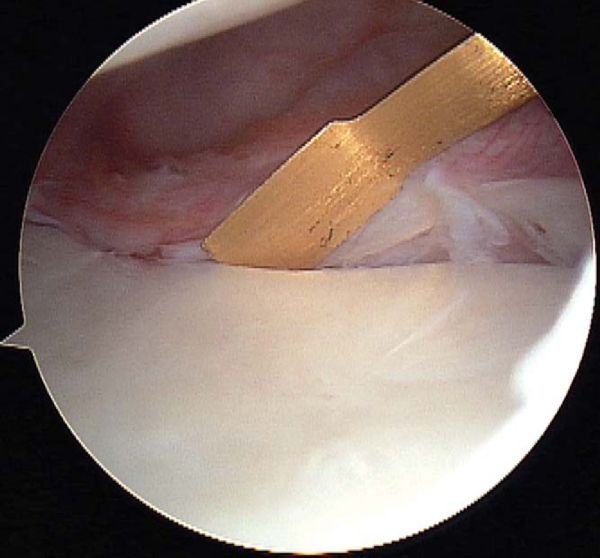

This step is crucial to prepare the capsulolabral tissue for repair. A sharp arthroscopic elevator (Liberator; ConMed Linvatec, Inc., Largo, Fla) is used to mobilize the capsulolabral tissue from the glenoid attachment (

Fig. 3-8

). Elevation should be performed until muscle fibers of the subscapularis are visible along the anterior glenoid neck. After mobilization, the capsulolabral tissue will be completely free, thus allowing superior translation for subsequent repair to the articular margin of the glenoid. A mechanical shaver or bur is used to abrade the anterior glenoid and to stimulate a bleeding bed to which the capsulolabral tissue will be reattached (

Fig. 3-9

). To better visualize the anterior glenoid during preparation, a 70-degree arthroscope may be used from the posterior portal to “look over the edge,” or the standard 30-degree arthroscope can be inserted down the anterosuperior portal while instrumenting through the anteroinferior portal.

Figure 3-8 |

Figure 3-9 |